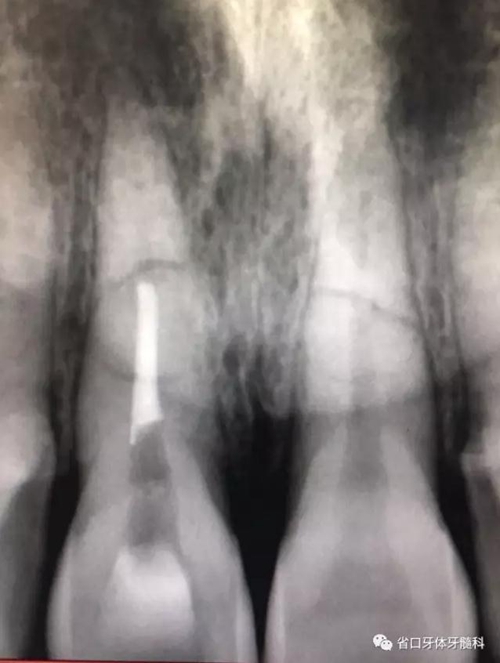

圖2 術(shù)前根尖片

X線片:11、21根中段見(jiàn)橫行根折線,無(wú)移位,根尖無(wú)明顯異常。